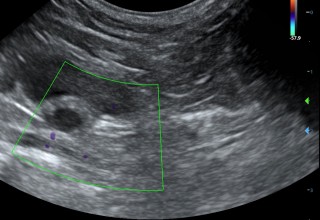

Echografie buik

Met een echo onderzoek kunnen we goed de organen bekijken. We bekijken en beoordelen het orgaan naar grootte, vorm en inhoud. Je kunt alle organen goed onderzoeken. Voor het beoordelen van de maag is het belangrijk dat het dier nuchter komt. Om de wand van de urineblaas goed te kunnen beoordelen moet de blaas gevuld zijn.

De organen die we routinematig beoordelen zijn:

Blaas - Prostaat - Baarmoeder/eierstokken - Lymfeklieren - Darmen - Nieren - Bijnieren - Milt - Alvleesklier - Maag - Lever

De buik in beeld

Hieronder zie je een aantal foto's van de buik met achtereenvolgens; blaasontsteking, blaastumor, vroege dracht hond 19 dagen, vergrote eierstok, lever, nier.